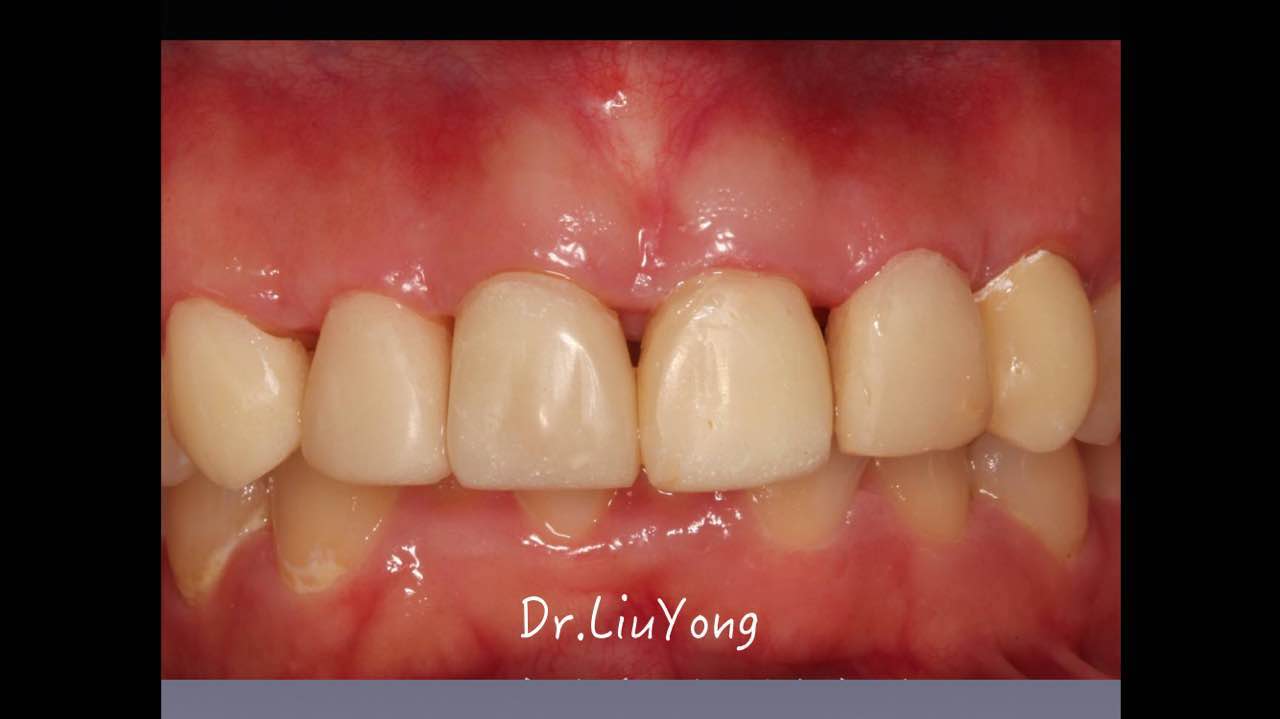

嚴重破壞生物學寬度,根尖瘺管,重行根管治療, 第一次冠延長建立唇腭側(cè)及鄰面BW,術后牙齦扇貝形差, 齦乳頭黑三角,再次行美學冠延長,建立牙齦扇貝形,手術免費, 患者因經(jīng)濟原因只能選擇鑄樁及鈷鉻合金烤瓷冠。終于完工